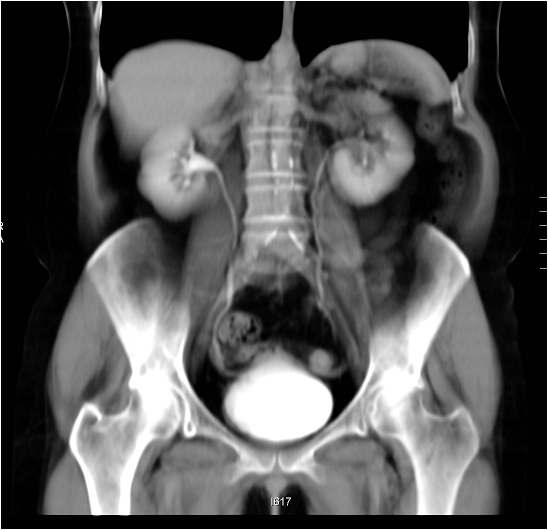

Image

Figure 12. Extensive right ovarian tumor.